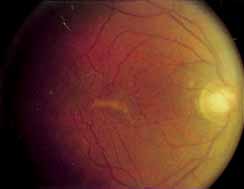

Although there is no reported genetic heterogeneity, there is wide phenotypic variation within the disorder. The major finding within the macula is a classic radial cystic maculopathy. Although retinal signs have been described in infants as young as 3 months, foveal schisis may be difficult to detect, leading to underdiagnosis. The diagnosis is usually not made until the affected male reaches school age (4 to 8 years of age) and encounters visual problems secondary to foveal involvement. Typical foveal schisis findings have been reported in 68% to 100% of eyes within various series.37,38 Foveal schisis is the only finding in about half the cases. It is characterized by the presence of radiate perifoveal microcysts located in the nerve fiber layer (Fig. 1) with radiate plications of the overlying internal limiting membrane that are seen especially well on monochromatic (red-free) photography (Fig. 2). The microcystoid change may slowly progress to form a macular cyst or hole. Foveal schisis has been reported in association with Goldmann-Favre vitreotapetoretinal dystrophy and rarely may be seen in rod-cone dystrophy or as an autosomal dominant or recessive condition.39–43